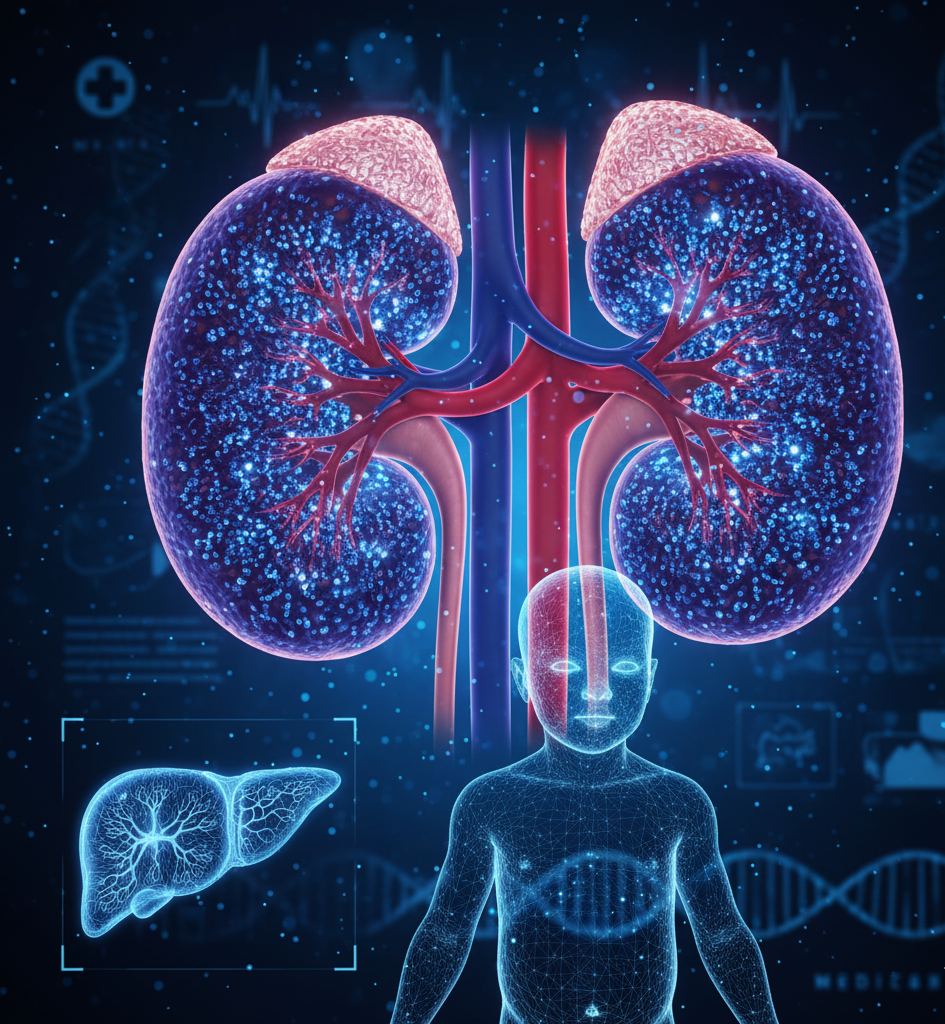

A Doença Renal Policística Autossômica Recessiva (DRPAR) é uma condição genética rara, caracterizada pelo desenvolvimento de múltiplos cistos nos rins desde a vida fetal ou infância. Diferente da forma autossômica dominante, que geralmente se manifesta na idade adulta, a DRPAR apresenta sintomas precoces e pode levar a insuficiência renal progressiva já nos primeiros anos de vida. O acompanhamento especializado por nefrologistas é fundamental para diagnóstico precoce e manejo adequado.

A DRPAR é causada por mutações em genes específicos, geralmente o PKHD1, que afetam a formação dos ductos renais e do fígado. Isso leva à formação de cistos nos rins e, frequentemente, alterações no fígado, como fibrose hepática congênita. A doença é herdada de forma autossômica recessiva, o que significa que ambos os pais precisam transmitir a mutação para que a criança seja afetada.

Os sinais da DRPAR variam conforme a idade, mas podem incluir aumento do volume abdominal, hipertensão, infecções urinárias recorrentes, insuficiência renal progressiva e alterações hepáticas. Em recém-nascidos, a doença pode causar insuficiência renal grave e hipertensão neonatal, sendo necessária avaliação imediata.

O diagnóstico é realizado através de ultrassonografia renal e hepática, que identifica cistos e alterações estruturais, exames laboratoriais que avaliam função renal (creatinina sérica, clearance de creatinina, proteinúria) e testes genéticos para confirmação da mutação. O acompanhamento de nefrologistas experientes é essencial para monitoramento da função renal e identificação precoce de complicações.

Não há cura definitiva para a DRPAR; o tratamento é de suporte e voltado para controlar sintomas e prevenir complicações. Isso inclui manejo da hipertensão, tratamento de infecções urinárias, acompanhamento da função renal e, quando necessário, preparação para diálise ou transplante renal. O acompanhamento multidisciplinar com nefrologista, pediatra e hepatologista é recomendado.